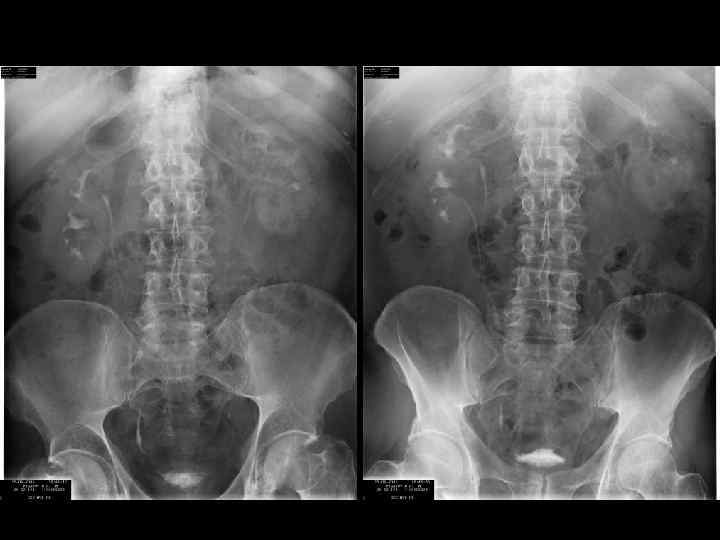

Нативная (обзорная) урография - анализ • Почки • Поясничные мышцы • область мочевых путей • скелет • добавочные тени

Нативная (обзорная) урография - анализ • • • Положение верхние концы Th 12 нижние концы L 3 Левая выше на 12 см продольные оси параллельны поясничным мышцам нижние концы смещены кпереди (30°)

Нативная (обзорная) урография - анализ Размеры не рентгенограммах • 11, 8 - 13, 8 • 5, 3 - 6, 6